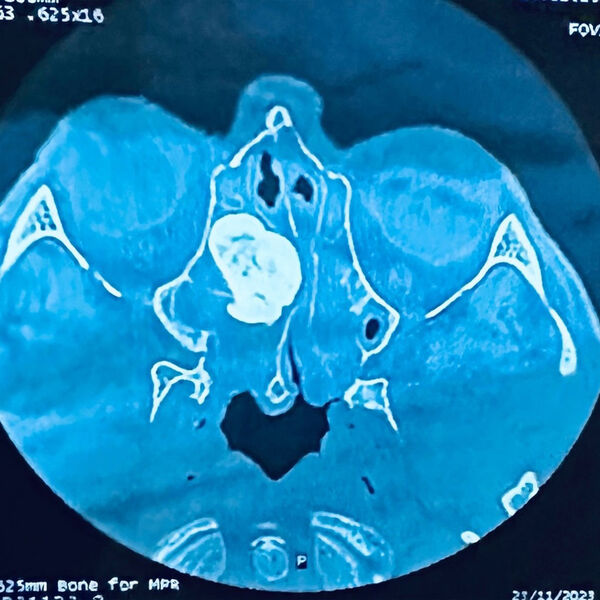

56-летний мужчина обратился в больницу с жалобами на затрудненное дыхание, постоянный насморк и сильные головные боли. В ходе обследования в носовых пазухах пациента была обнаружена доброкачественная опухоль большого размера.

Остеома блокировала соустья с пазухами носа, препятствуя оттоку слизи и аэрации пазух. Было принято решение о проведении малоинвазивной операции, без единого разреза медики удалили новообразование. Спустя несколько дней пациента выписали на амбулаторное лечение.